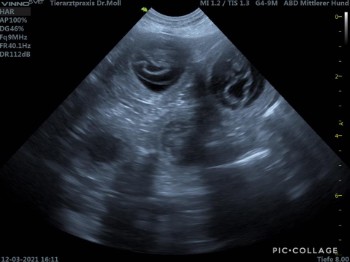

Hochzeit am 13.02.2021 | | Ultraschall am 13.03.2021 (28. LT) |